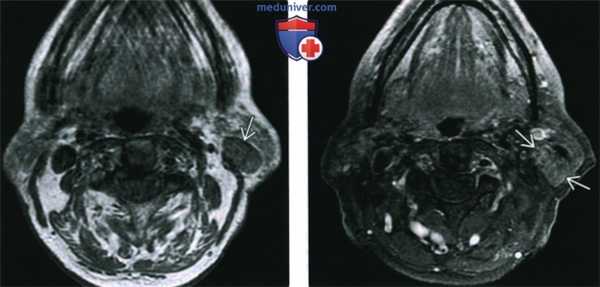

(Слева) На аксиальной КТ с КУ в поверхностной доле околоушной железы определяется хорошо отграниченная опухоль в с толстым периферическим «ободком», накапливающим контраст, и кистозным участком в центре. Такая лучевая картина характерна для мукоэпидермоидного рака (МЭР) низкой степени злокачественности.

(Справа) На аксиальной КТ с КУ в околоушной железе визуализируется опухоль с расплывчатой наружной границей и четкой внутренней границей. Опухоль равномерно накапливает контраст. Картина ожидаема для МЭР промежуточной степени злокачественности, хотя и не является специфичной. (Слева) На аксиальной КТ с КУ визуализируется большая неоднородная опухоль с нечеткими краями, с кистозными участками, неравномерно накапливающая контраст. Определяется инвазия жевательной мышцы. Такая картина характерна для МЭР высокой степени злока -чественности.

(Слева) КТ с КУ, аксиальная проекция: в поверхностной доле околоушной железы определяется образование с четкими контурами. Оно имеет плотное кольцо накопления контраста, в центре находится зона некроза или киста. Такой вид образования достаточно характерен для мукоэпидермоидною рака низкой степени злокачественности.

(Справа) КТ с КУ, аксиальная проекция. Новообразование околоушной железы, с латеральною края железа имеет нечеткий контур, медиальный край железы четкий. Опухоль равномерно накапливает контрастное вещество. И хотя такая картина достаточно неспецифична, так должен выглядеть мукоэпидермоидный рак промежуточной степени злокачественности. (Слева) КТ с КУ, аксиальная проекция: определяется крупное гетерогенное новообразование с нечеткими контурами и неоднородным контрастированием. В центре отмечается кистозный участок. Опухоль прорастает в жевательную мышцу. Такая картина характерна для мукоэпидермоидною рака высокой степени злокачественности.